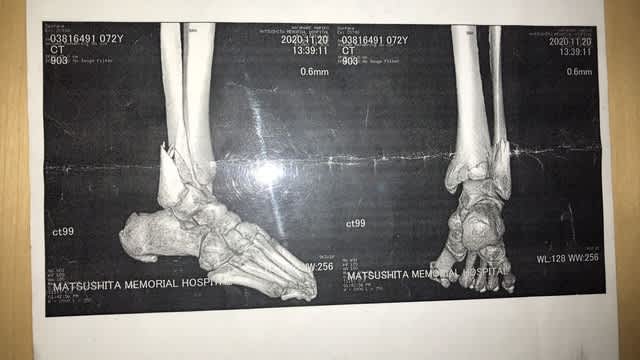

病名『右足関節脱臼骨折』です( ̄□ ̄;)!!